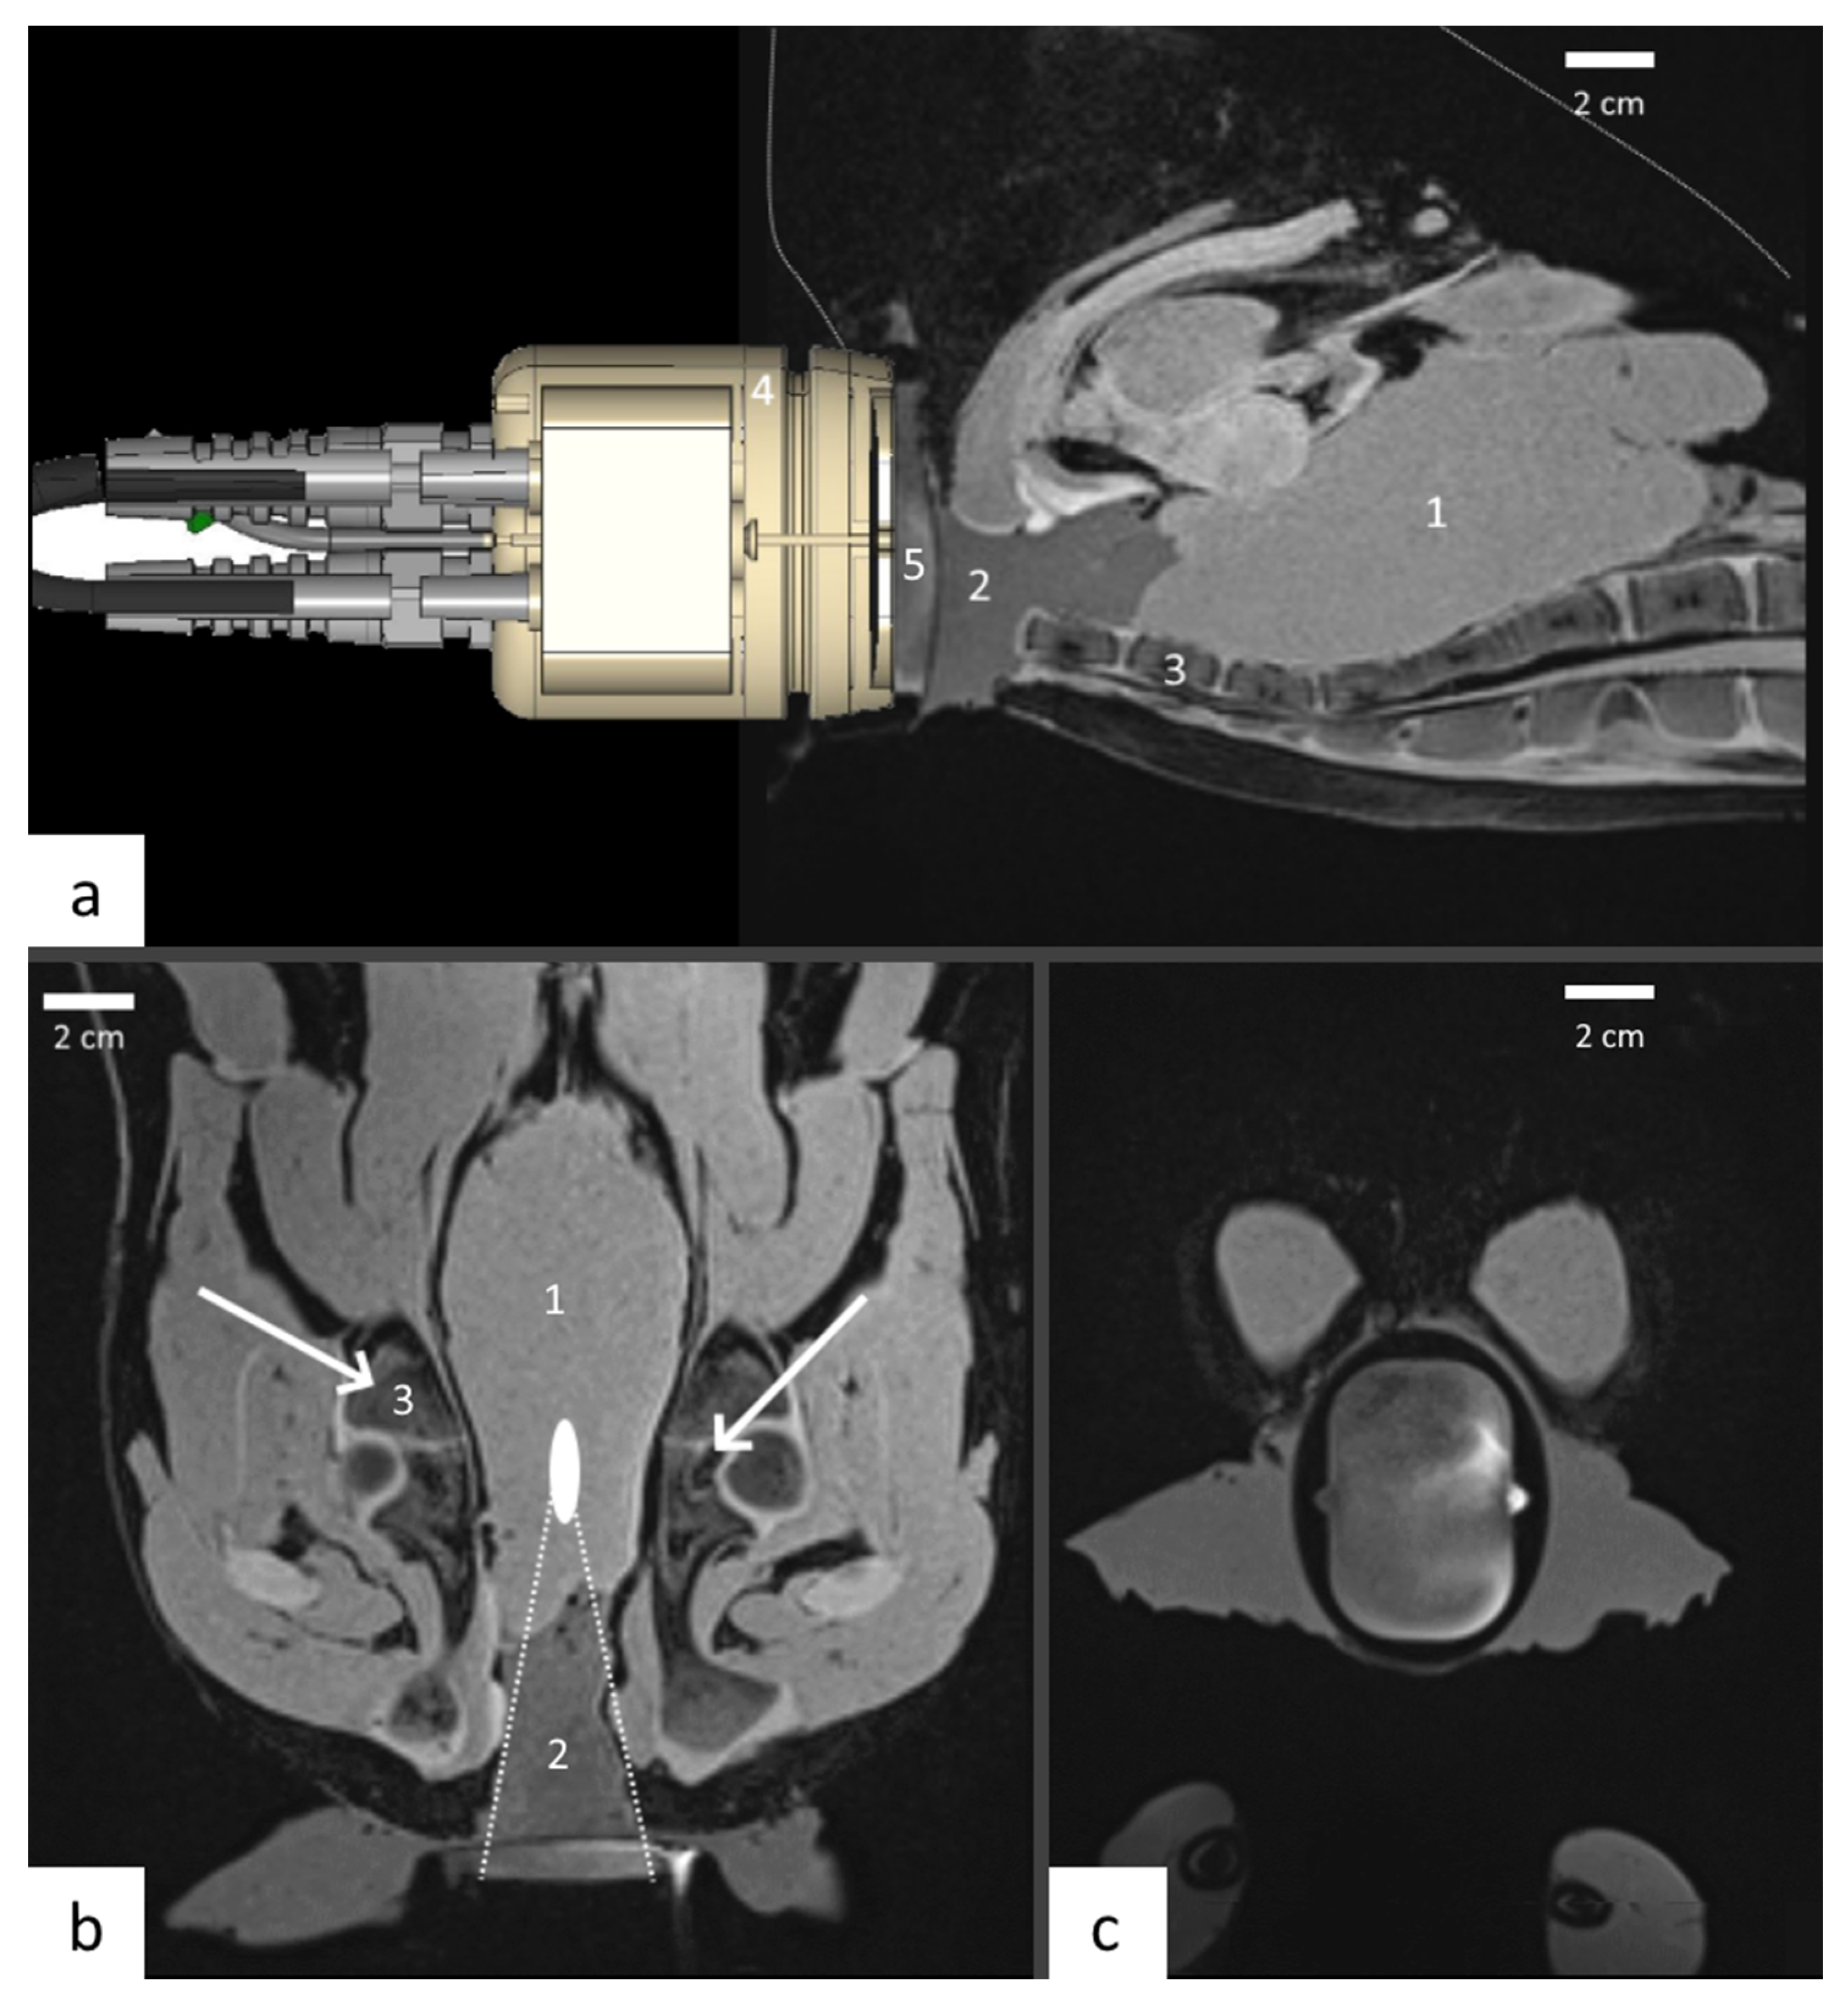

2.5. MRI Guidance of Local Hyperthermia

2.7. Ex-Vivo Studies

3.1. Transducer Design

3.2. Performance Test in Tissue Mimicking Gel

3.3. Ex Vivo Test

- Guillemin, P.C.; Dipasquale, G.; Uiterwijk, J.W.; Jaccard, M.; Lorton, O.; Tsoutsou, P.; Gariani, J.; Poletti, P.-A.; Salomir, R.; Zilli, T. Magnetic resonance-guided ultrasound hyperthermia for prostate cancer radiotherapy: An immobilization device embedding the ultrasound applicator. J. 3D Print. Med. 2022, 6, 55–67. [Google Scholar] [CrossRef]